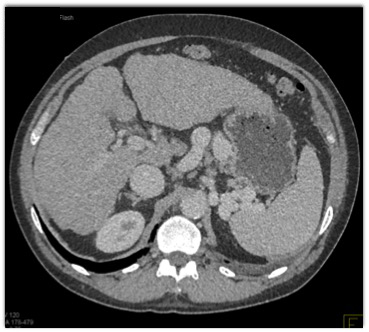

The most critical diagnosis in this case is?

cirrhosis

portal hypertension

hepatoma

varices